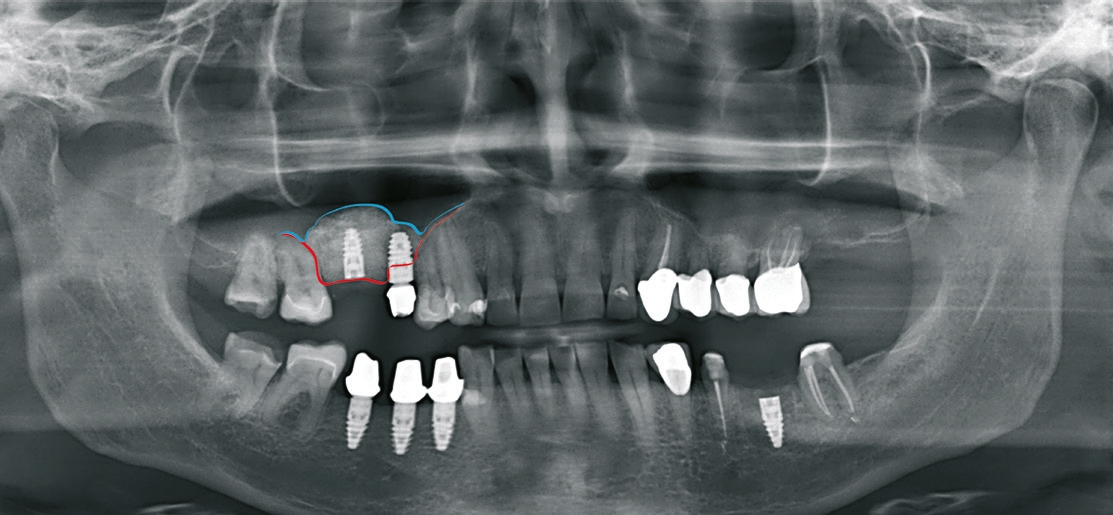

Patient 2: männlich, 71 Jahre alt, Anamnese: koronare Herzkrankheit; Diagnose: zahnloser Kiefer resp. nicht erhaltungswürdiger Zahn 11, insuffizienter Zahnersatz. Knochenersatzmaterial: maxgraft® (botiss) (Abb. 11 und 12).

Dr. van Orten